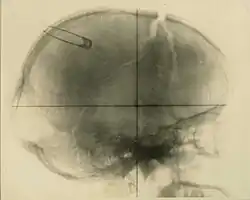

Signes radiologiques

Les lésions osseuses peuvent être totalement absentes malgré une atteinte cérébrale[18].

- Fracture avec enfoncement/Embarrure : l'os du crâne (frontal, occipital, pariétal ou temporal) est fracturé et des fragments osseux sont enfoncés, ce qui peut occasionner une blessure ou une compression sur le cerveau.

- Fracture de la base du crâne : l'os sphénoïde est fissuré. Lésions généralement linéaires.